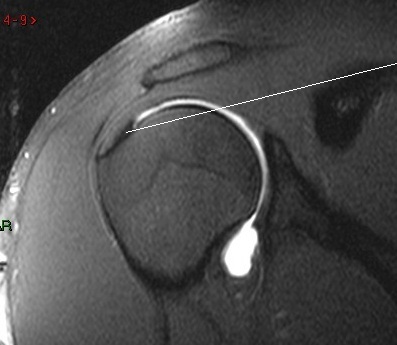

MRI of rotator attaching to bone. This attachment is torn off when there is a tear of the  Rotator Cuff.

After a fall, a wrenching injury to the shoulder or perhaps with no warning the rotator cuff tendon can tear off its bony attachment.